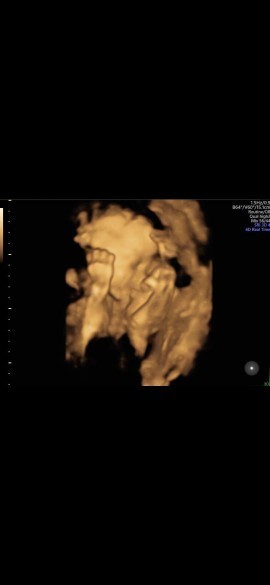

Bunda,mw cerita ni,q hmil dh 36 week,pas usg posisi ank kpl dh dbwh,air ktuban bgs,intiny bgus lh bun tuk lhiran normal,usia sy kn thn ini 29 thn,3 thn nikah bru d ksh dedek dlm prt.dan td saya kaget dg dr yg sarani sy tuk sc bun.padahal sy dh lakuin biar bs normal.alasanny krn fktor umur n lm dptny,ktny lbh baik mnyakiti 1org sj dr pd skit k2 ny.. sy lgsg down bunda2..apa ad yg sm dg sy,n ad saran gk bun sy hrs gmn..#seriusnanya #bantusharing